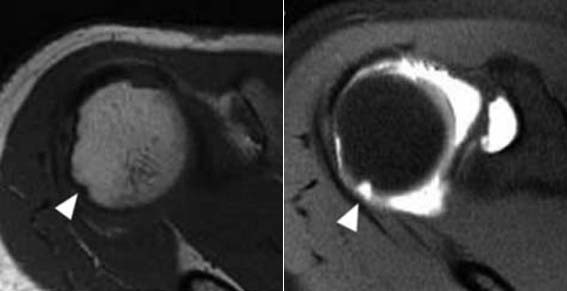

| | ¡è¡è ¡ã³»½Ã°æÀû ¹Ì¼¼ õ°ø¼úÀ» ÀÌ¿ëÇÑ »ó¿Ï°ñµÎ º´º¯ Ä¡·á¹ý <»çÁøÁ¦°ø=õ¾È¾Æ»êÃæ¹«º´¿ø> | ¨Ï ¿Â¾ç½Å¹® | |

| | ¡è¡è ¡ã¼ö¼ú Àü ÈÄ MRI¸¦ ºñ±³ÇßÀ» ¶§ »ó¿Ï°ñµÎÀÇ º´º¯ÀÌ È¸º¹µÊÀ» °üÂû <»çÁøÁ¦°ø=õ¾È¾Æ»êÃæ¹«º´¿ø> | ¨Ï ¿Â¾ç½Å¹® | |